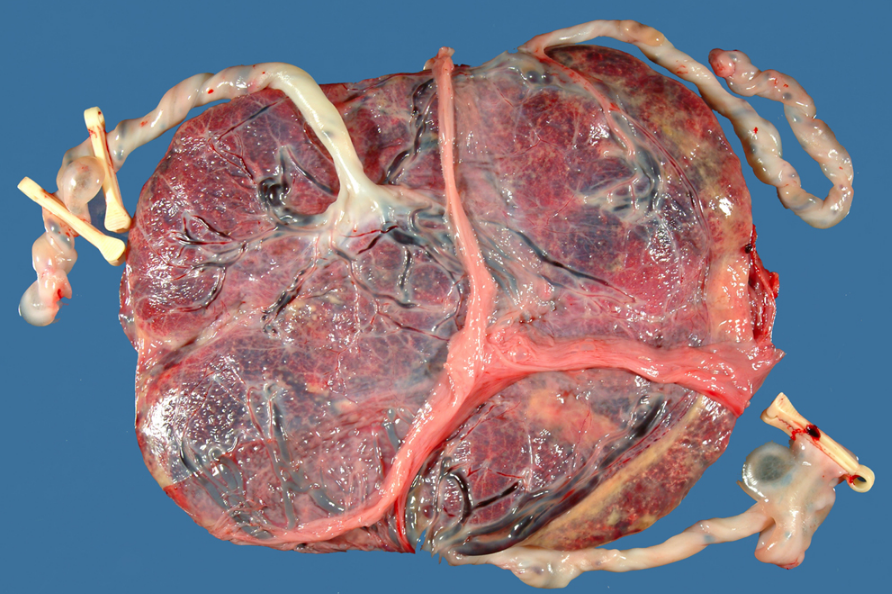

Placenta

Le placenta est un organe formé par l’accolement de membranes d’origine maternelle et fœtale (trophoblaste), irriguées par des vaisseaux. Il se structure pendant les cinq premiers mois de la grossesse, puis continue à grandir mais sans rien modifier à sa structure. Il sera expulsé naturellement environ une demi-heure après la naissance et, dans certaines cultures (mais pas en France, où le placenta est considéré comme un déchet hospitalier et incinéré), il donne lieu à des rituels tels que l’enfouissement dans le jardin, parfois la consommation du placenta sous forme de smoothie ou encore le conditionnement en gélules pour bénéficier de supposées vertus bénéfiques. Quand le terme de la grossesse est dépassé, le placenta devient moins fonctionnel et le foetus est alors moins bien nourri et oxygéné. D’où la nécessité d’un déclenchement.

Le placenta est essentiel durant votre grossesse puisqu’il sert de plate-forme d’échanges entre la mère et le bébé, secrète des hormones et protège le fœtus. Le placenta remplace le tube digestif et les poumons du futur bébé, qui sont encore immatures. Les nutriments (sucres, minéraux) ou certaines hormones sont reçus par le bébé par l’intermédiaire du placenta. Il laisse passer les virus jusqu’au 5e mois, c’est pourquoi certaines pathologies qui peuvent causer des malformations foetales sont à prévenir. Certains médicaments, ou certaines substances nocives comme le tabac ou l’alcool, peuvent aussi passer la barrière placentaire et avoir un effet délétère. Mais heureusement beaucoup de maladies peuvent être évitées grâce aux anticorps de la mère que le placenta laisse passer également, anticorps qui seront actifs jusqu’à 6 mois après la naissance. Après le 5e mois, le foetus est capable de fabriquer ses propres anticorps. Le placenta a aussi une fonction essentielle de protection contre beaucoup de bactéries.

Parfois, le placenta peut engendrer des complications : c’est le cas lorsqu’il est placé trop bas (placenta praevia) par exemple. Dans ce cas, il gêne l’ouverture du col de l’utérus, et peut même, dans des cas extrêmes, provoquer des saignements à la moindre contraction au cours du troisième trimestre. Grâce à l’échographie, le placenta praevia peut être dépisté très tôt, dès le début du second trimestre. L’accouchement par voie basse est impossible donc une césarienne s’impose, souvent deux à trois semaines avant le terme. Lorsque le placenta est situé à l’orifice interne du col (placenta prævia marginal), l’accouchement par les voies naturelles est possible, sous surveillance renforcée.

Autre complication, le décollement du placenta (hématome rétroplacentaire) pendant la grossesse. Souvent cause de fausse couche, c’est une urgence obstétricale et lorsque la date de l’accouchement approche, une césarienne est décidée.

Enfin, le placenta accreta définit une insertion du placenta dans la couche musculeuse interne de la paroi utérine dite myomètre. C’est une pathologie grave qui peut présenter des complications obstétricales très sérieuses (hémorragie du post-partum). On retrouve souvent le placenta accreta en cas de placenta inséré bas sur une cicatrice de césarienne ou dans le cas de grossesses répétées ou encore si la femme a subi plusieurs curetages.